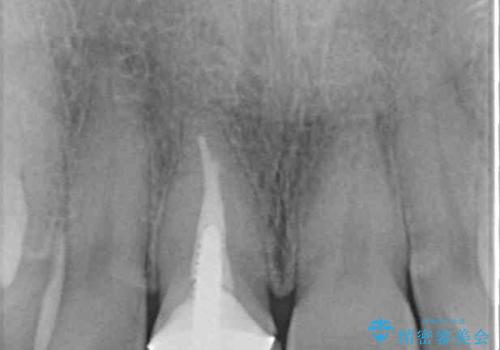

奥歯は虫歯が放置されていましたが、特に症状はなく歯髄の状態も正常でした。

前歯、奥歯ともにオールセラミッククラウンやセラミックインレーにて治療を行うこととしました。